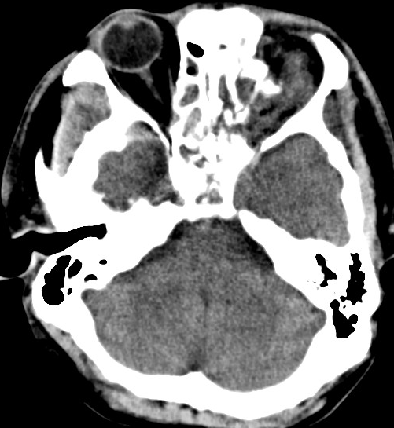

2014-10-5 CT